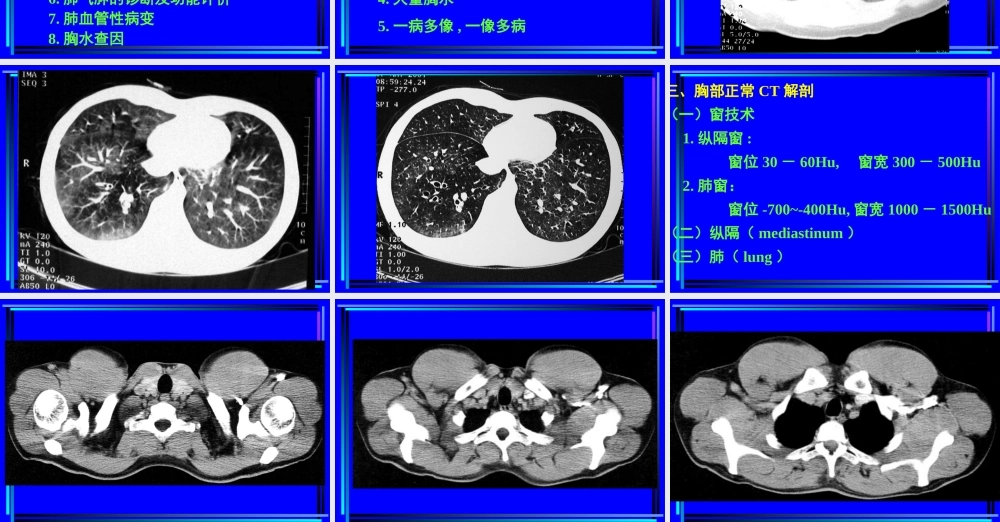

胸部CT诊断第一节胸部CT检查一、胸部CT扫描方法(一)普通扫描(平扫plainCTscan)(二)增强扫描(contrastenhancement,CE)1.注药方法团注法(bolusinjection)静滴法2.扫描程序静态CT扫描动态CT扫描(dynamicCTscan)(三)特殊扫描1.薄层扫描2.高分辨率CT扫描(HighresolutionCT,HRCT)3.CT血管造影(CTangiography,CTA)4.心电门控扫描二、CT对胸部疾病的诊断价值与限度(一)诊断价值1.肺部小病灶与早期病变2.咯血查因3.肺不张、肺实变4.肺肿瘤分期5.肺弥漫性病变6.肺气肿的诊断及功能评价7.肺血管性病变8.胸水查因(二)影响CT检出与诊断的因素(主要为常规CT)1.运动伪影2.部分容积效应3.层厚与层间距4.大量胸水5.一病多像,一像多病三、胸部正常CT解剖(一)窗技术1.纵隔窗:窗位30-60Hu,窗宽300-500Hu2.肺窗:窗位-700~-400Hu,窗宽1000-1500Hu(二)纵隔(mediastinum)(三)肺(lung)第二节肺部疾病的CT诊断一、先天性疾病1.肺隔离症(pulmonarysequestration)某一肺段和正常肺组织及气管和支气管树相互分离,无呼吸功能,血供来自主动脉系统,分叶内型和叶外型两类。CT表现:部位:两下肺、脊柱旁。形态:囊实性或囊性或实性,邻近肺野斑片状影。血供:体循环,病灶内血管异常。鉴别诊断:支气管源性囊肿、肺脓肿、先天性膈疝。2.支气管囊肿(bronchogeniccyst)为支气管的先天发育异常,根据组织学来源可分为支气管囊肿和支气管肺囊肿(pulmonarybronchogeniccyst)。CT表现:部位:纵隔与肺的任何部位,多见于气管隆突5cm范围内。形态:圆形、椭圆形、边缘锐利,壁菲薄。密度:均匀,可有出血和液气平,壁可强化。支气管扩张症(bronchiectasis)因:先天性或后天性理:肉眼观,支气管呈柱状、囊状、静脉曲张状或混合状扩镜下观,粘膜柱状上皮呈急、慢性炎性改变,伴弹力纤平滑肌和软骨的损害CT表现:病变支气管壁增厚,管腔扩大,形态多样。1.柱状扩张:“双轨”征、“印戒”征。2.囊状扩张:葡萄串状、卷发样。3.曲张形扩张:粗细不均的囊柱状。4.混合型合并粘液栓时,腔内可见棒状或结节状软组织密度影,咳痰后可消失,同时可见肺野内出血,继发感染等征象。三、肺感染性病变1.支气管肺炎支气管肺炎(bronchopneumonia)或小叶性肺炎(lobularpneumonia)病理:小支气管壁充血、水肿、间质炎性细胞浸润,小叶渗出、实变、气肿或不张。CT表现:两肺中下野中内带,支气管血管束增粗,沿其分布小斑片影及边缘模糊的小结节影。...